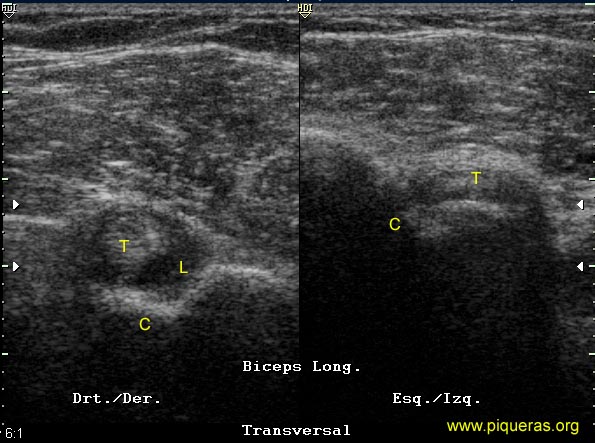

Tenosinovitis

del Bíceps (imagen 3D)

Mujer de

66a con imagen típica de sinovitis en la vaina

del bíceps derecho. Presenta una imagen típica

en 'ojo de buey' en el corte ecográfico transversal.

el bíceps izquierdo está subluxado fuera

de la corredera.